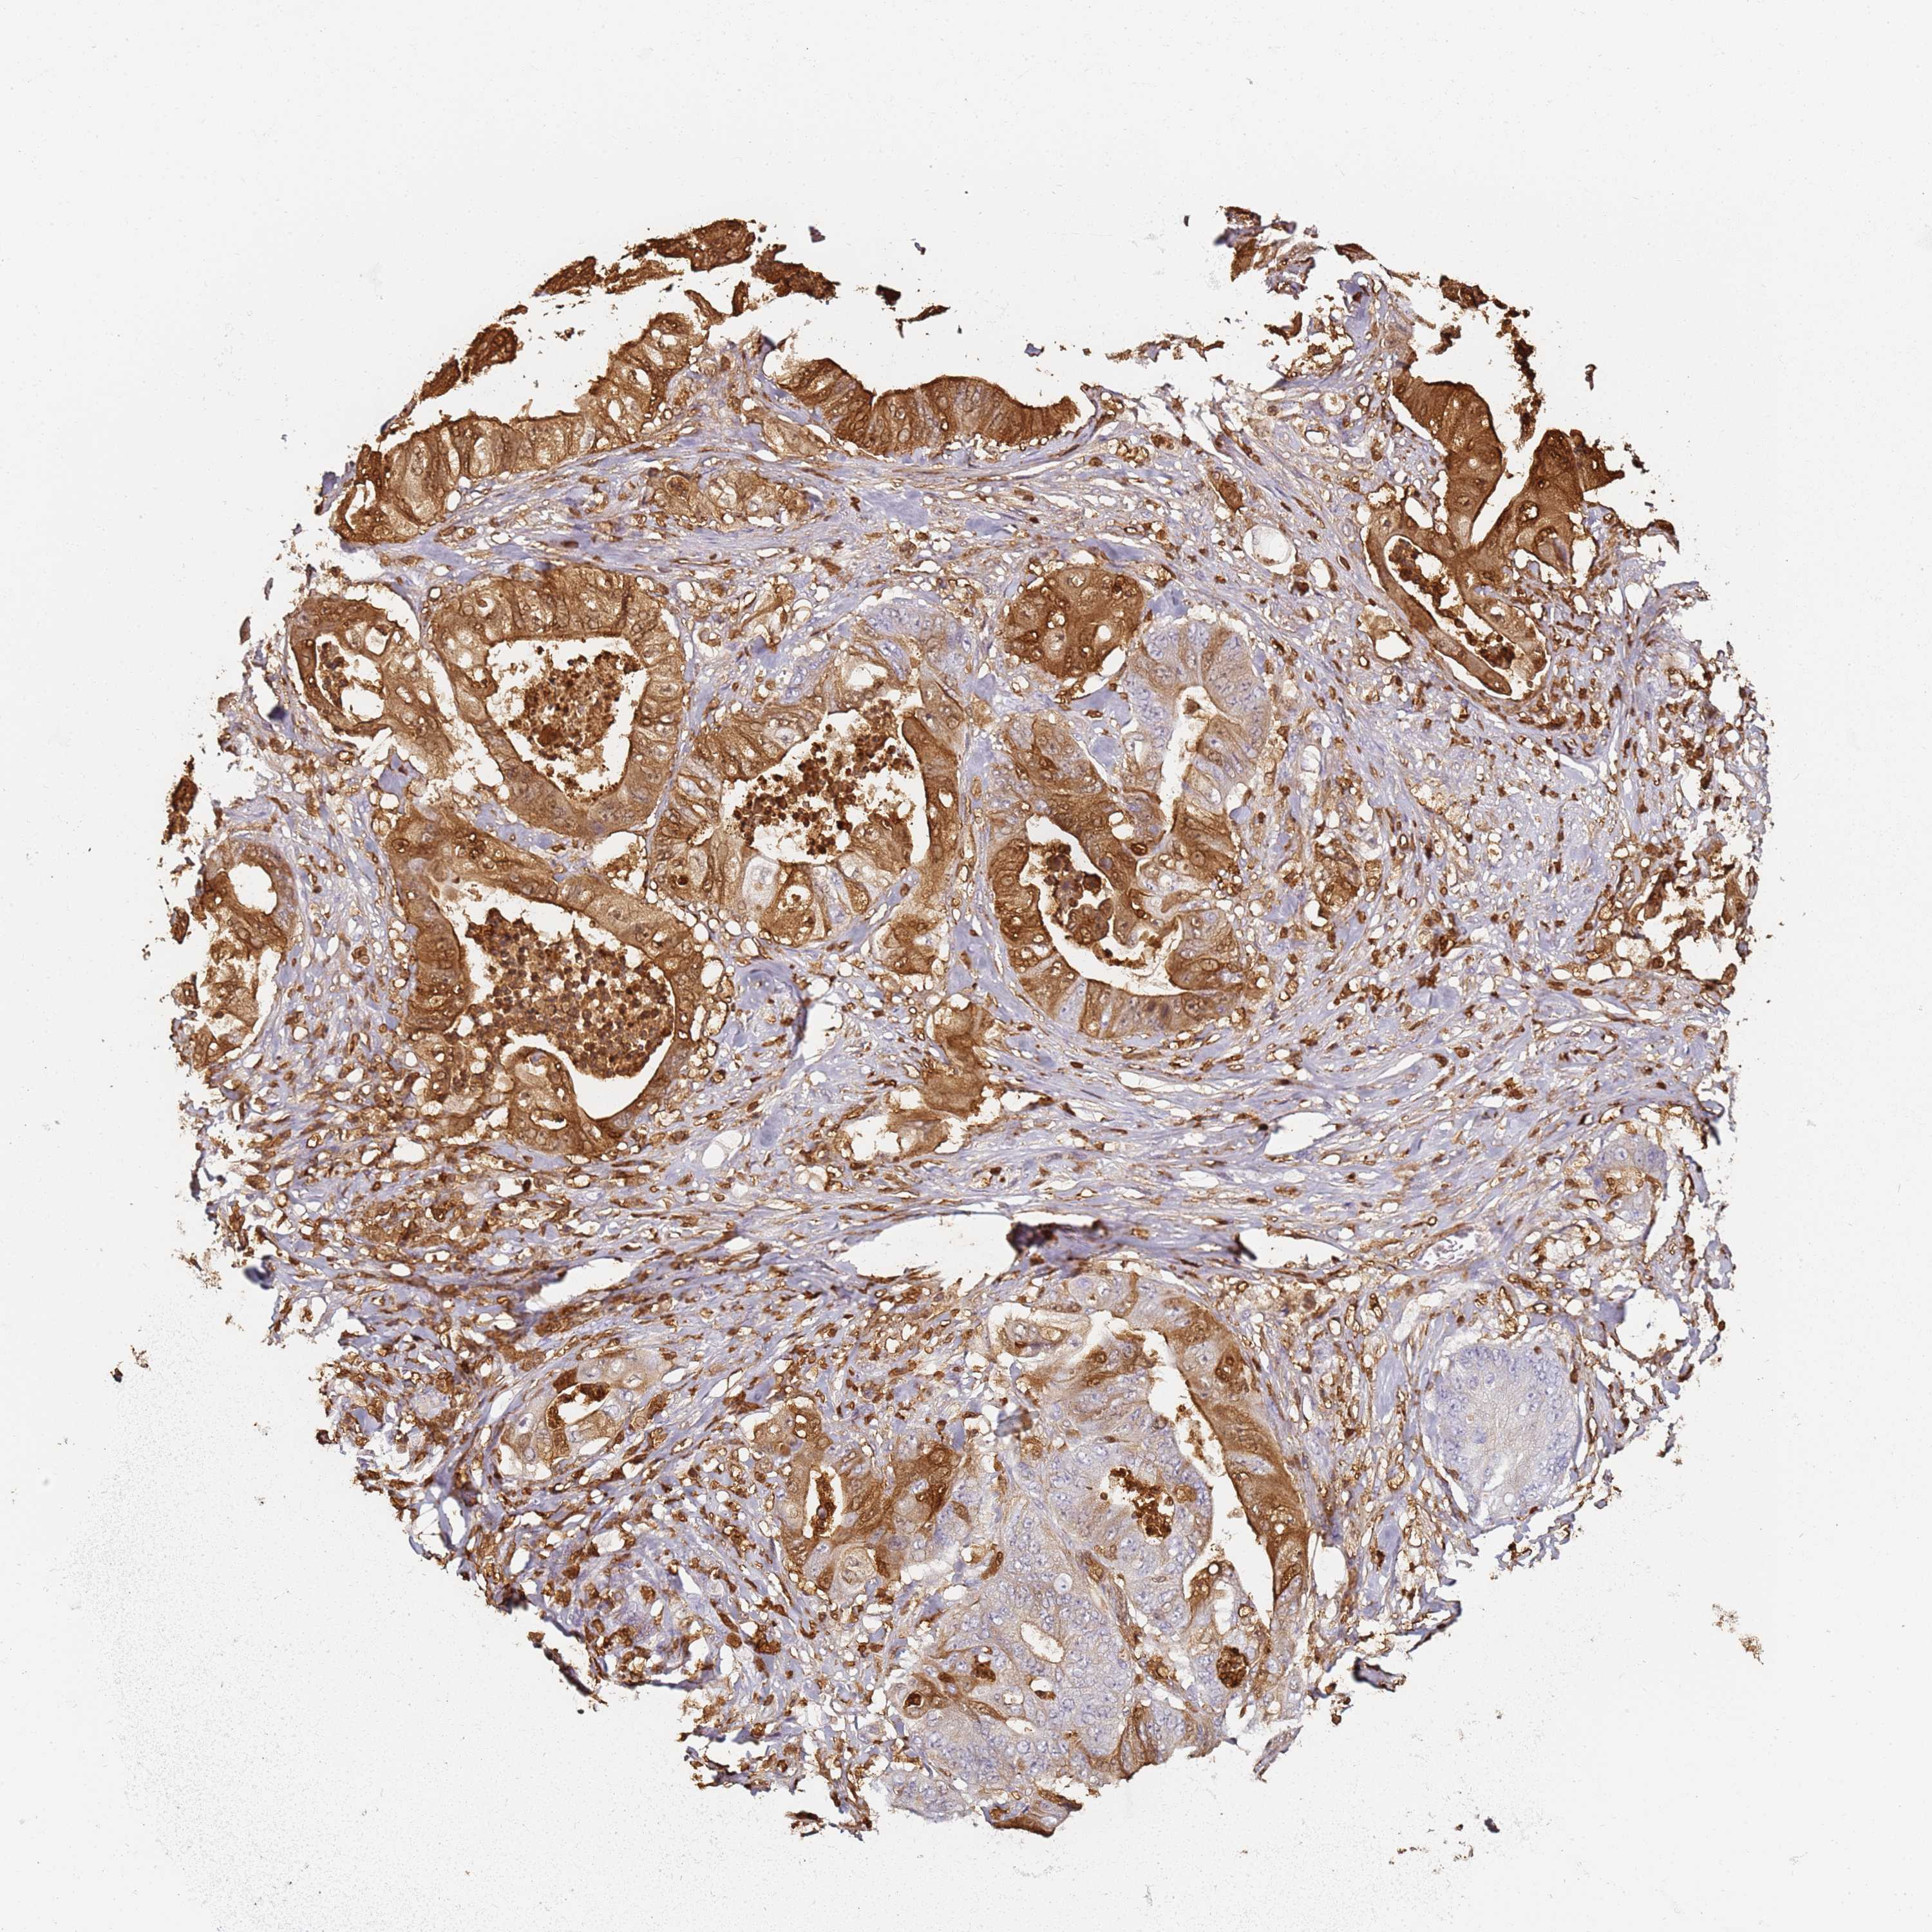

STOMACH CANCER - Protein expressioni

A mouse-over function shows sample information and annotation data. Click on an image to view it in a full screen mode. Samples can be filtered based on level of antibody staining by selecting one or several of the following categories: high, medium, low and not detected. The assay and annotation is described here.

Note that samples used for immunohistochemistry by the Human Protein Atlas do not correspond to samples in the TCGA dataset.

Antibody stainingi

Antibody staining in the annotated cell types in the current human tissue is reported as not detected, low, medium, or high, based on conventional immunohistochemistry profiling in selected tissues. This score is based on the combination of the staining intensity and fraction of stained cells.

Each image is clickable and will lead to virtual microscopy that enables deeper exploration of all samples and also displays staining intensity scores, fraction scores and subcellular localization as well as patient and tissue information for each sample.

HPA007973

CAB002618

CAB027387

CAB058698

CAB068227

CAB068228

Adenocarcinoma, NOS